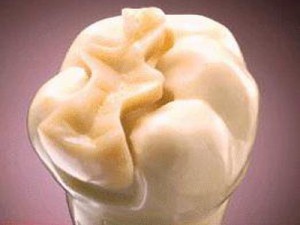

- INLAY: Incrustación que no abarca ninguna cúspide dental

- ONLAY: Incrustación que abarca al menos una cúspide sin cubrirlas todas.

- OVERLAY: Cubrimiento cuspídeo completo.

- ENDOCORONA: Cubrimiento cuspídeo completo en dientes desvitalizados, que utiliza la cámara pulpar com sistema antirrotatorio.